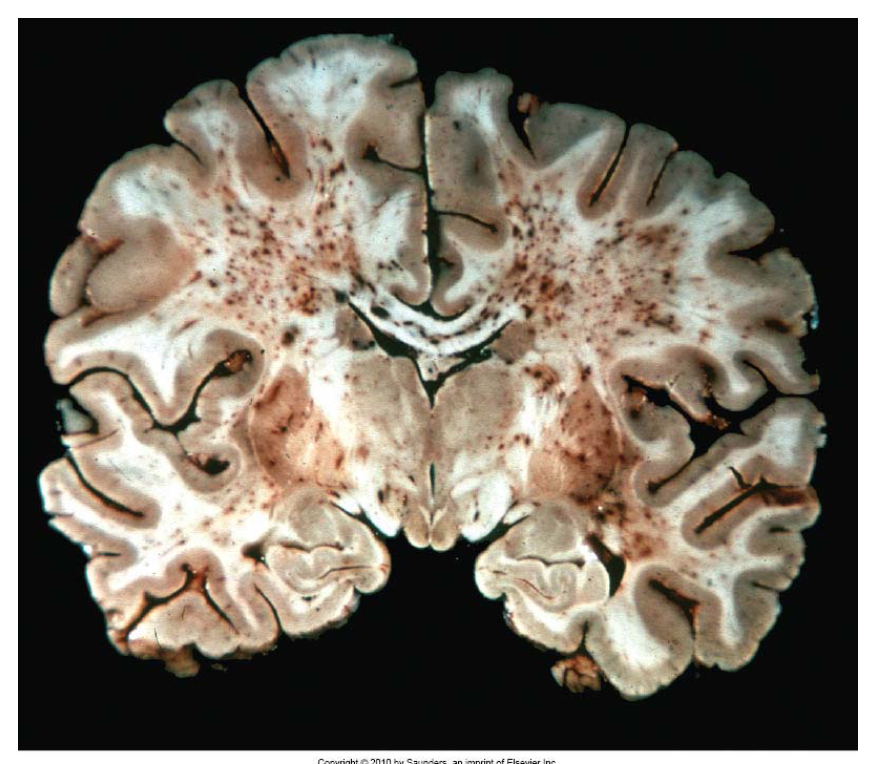

What pathology is shown in the provided image?

MS

wel circumscribed, tan, irregularly shaped plaque in periventricular white matter (demyelinating)

plaques (red arrows) seen around the 4th ventricle